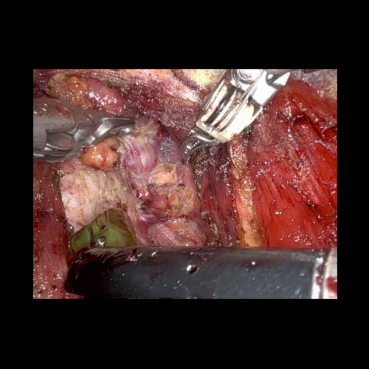

The medical images considered are obtained from a video of a surgery called Bilateral Axillo-Breast Approach (BABA) robotic thyroidectomy, approved by the Research Ethics Committee of Seoul National University Bundang Hospital (B-2504-969-701). This is a thyroid surgery method that is representative of remote access surgery. Clinically, BABA surgery is well known for its superior cosmetic effects and lower complications than conventional thyroidectomy. This surgical method creates surgical incisions in both axillae and both areolas and uses the da Vinci robot to perform the surgery. The surgical video is recorded during the surgery, and the high-resolution images captured are analyzed to develop meaningful clinical studies. Therefore, encoding a high quality of image into a quantum circuit may be significantly important for the future of clinical studies.

We performed similar numerical simulations for more images taken at different frames. Fig. 5 compares the original zero-padded images, the corresponding reconstructed images using FAQPIE with and without the combination of two compression techniques with the same parameter setting as in Fig. 4. A similar observation is made that encoding the images with the two compression techniques results in more efficient FAQPIE with reasonable surgical details and lowered gate counts, as summarized Table 3.

Refer to caption

Figure 5: Comparison of original medical images (left), the corresponding reconstructed images via FAQPIE with no compression technique (middle) and the two compression techniques applied as in Fig. 4 (right).